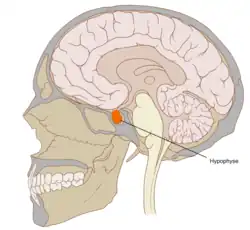

Die Hypophyse (auch griechisch-lateinisch Hypophysis cerebri und kurz Hypophysis, von altgriechisch ὑπόφυσις hypóphysis „das unten anhängende Gewächs“) oder Hirnanhangdrüse, lateinisch Glandula pituitaria, ist eine an der Basis des Gehirns „hängende“, etwa erbsengroße Hormondrüse, die vom Hypothalamus gesteuert wird und der eine zentrale übergeordnete Rolle bei der Regulation des Hormonsystems im Körper zukommt. Sie ist eine Art Schnittstelle, mit der das Gehirn über die Freisetzung von Hormonen Vorgänge wie Wachstum, Fortpflanzung und Stoffwechsel reguliert. Die Hypophyse sitzt dem Türkensattel (Sella turcica), einer knöchernen Vertiefung der mittleren Schädelgrube auf Höhe der Nase, auf.